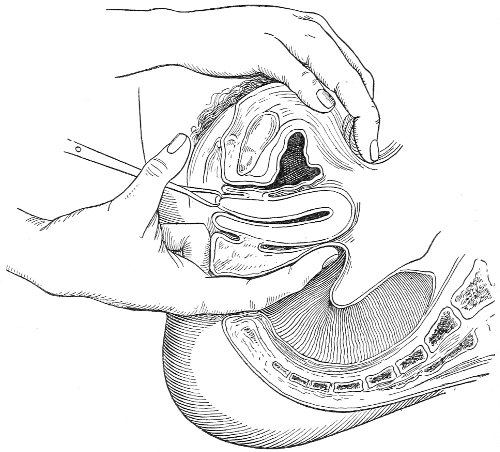

In making the bimanual examination the structures 25 should be palpated methodically in order. The vaginal finger notes the condition of the cervix uteri. If the fundus be in the normal position, the uterus can then be taken between the abdominal hand (upon the fundus) and the vaginal finger (upon the cervix) (Fig. 3). The shape, size, mobility, and consistency are noted. The vaginal finger is then passed anteriorly and laterally toward either uterine cornu, while the abdominal fingers pass over to the posterior aspect of the same cornu. The ovarian ligament and the proximal end of the Fallopian tube may thus be felt. Passing farther outward, the whole of the tube and the ovary may be examined. The same procedure is then applied to the opposite side.

Fig. 3.—Bimanual examination; median sagittal section of the pelvis.

The examination of the uterus and other pelvic structures is often facilitated by dragging the uterus downward with a tenaculum while the vaginal or the bimanual examination is being made. Sensation in the cervix is so slight that little or no pain is experienced in this procedure. The anterior or posterior lip of the cervix is caught with the single or the double tenaculum (Fig. 4), guided along the vaginal finger or introduced through the speculum, and the uterus is drawn down by an assistant in case the bimanual examination is being made, or by the external hand of the examiner in case a simple vaginal examination is made. When this is done the utero-sacral ligaments are made tense, and can be felt like two cords extending from the sides of the cervix outward and backward to the pelvic wall. The posterior surface of the uterus can be palpated often as high up as the fundus. The method is especially useful when the examination is made by the rectum, and in this way the whole posterior surface and the fundus of the uterus may be palpated (Fig. 5).

Fig. 5.—Bimanual examination with one finger in the rectum. The uterus is drawn down with the double tenaculum.